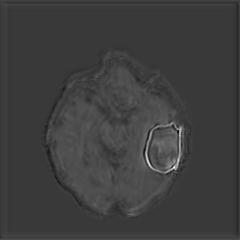

(a) (b) (c) (d)

Boundary Stream:

Fig. 2 demonstrates the output of each of the attention layers in our dedicated boundary stream. In essence, each attention layer progressively localizes the tumor and refines the boundaries. The first attention layer has learned rough estimate of the boundaries around the tumor and localized it, whereas the second and third layers have learned more fine-grained details of the edges and boundaries, refining the localization. Moreover, since our architecture leverages a dilated spatial pyramid pooling to merge the learned feature maps of the regular segmentation stream and the boundary stream, multiscale regional and boundary information have been preserved and fused properly, which has enabled our network to capture the small structural details of the tumor.

(a) (b) (c) (d) (e)